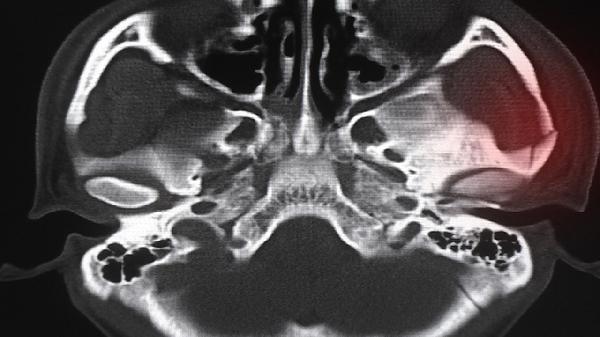

超声检查可显示输卵管增粗、盆腔积液或输卵管卵巢脓肿,经阴道超声分辨率更高。CT或MRI适用于复杂病例,能清晰显示脓肿范围及周围组织受累情况。影像学检查无特殊准备要求,但需避开经期以获得更准确结果。对于不孕患者,子宫输卵管造影可评估输卵管通畅程度。